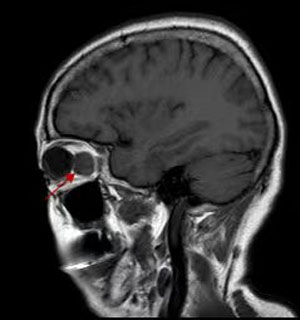

B超、CT、核磁共振等影像学检查都必不可少,可以提供病变的位置、大小。细针穿刺活检创伤小,但可以获取细胞学标本,帮助诊断。有的病例需要手术活检进行病理检查明确诊断,指导治疗。

就肿瘤而言,手术完整摘除是最常用的治疗手段,由于在眼眶有限的空间内,集中了眼球、视神经、眼外肌、供养血管等重要结构,因此手术是有难度的。医生根据眼眶肿瘤的位置选择最佳的手术路径,借助于先进的头戴放大镜系统,使手术操作更加准确,最大程度减少了并发症。